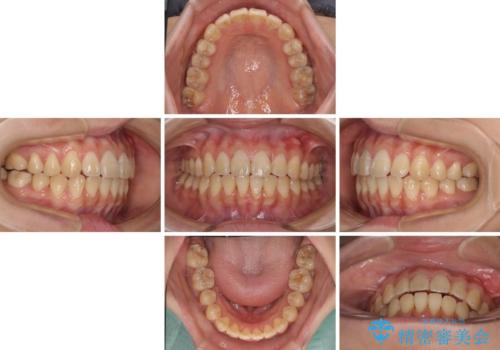

舌の突出癖による開咬と前歯の突出 インビザライン矯正治療

矯正治療の途中で前歯の根管治療とオールセラミッククラウンによる補綴治療を行い、その後インビザライン1セットを用いて細かい部分を仕上げました。